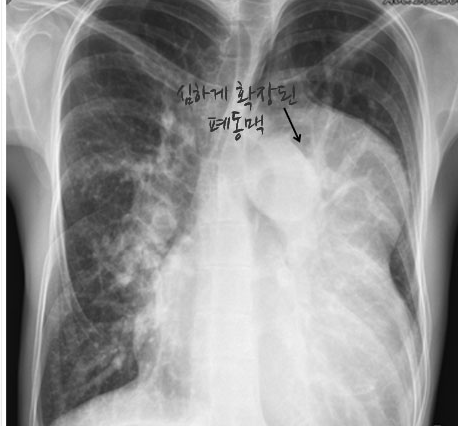

심방 중격 결손, 심실 중격 결손, 혹은 동맥관 개존증과 같이,심장 안이나 밖에서 왼쪽 심장 (체순환)에서 오른쪽 심장 (폐순환)으로 혈류가 바로 흘러 버리는 단락 (좌->우 단락)이 지속되는 심장병을 교정하지 않고 그냥 두면,폐동맥에 흐르는 혈류량이 증가되어 결국 폐동맥을 손상시키고, 결국 폐순환에 체순환의 혈압을 웃도는 고혈압이 생깁니다.이렇게 되면 혈류는 전신을 돌며 산소를 공급하고 돌아온 산소가 부족한 오른쪽 심장의 혈액이 왼쪽 심장으로 넘어가(우->좌 단락)산소가 부족한 피가 다시 전신을 순환하게 되므로 청색증이 생깁니다. 이러한 상황에 이르렀을 때, 아이젠멩거 증후군이 발생하였다고 합니다.

아이젠멩거 증후군이 진단되면 원래 가지고 있던 심장 결손은 대부분의 경우 교정이 불가능합니다.

간혹, 아이젠멩거 증후군을 진단받은 환자들 중에서도 장기간의 내과적 치료 후, 비가역적으로 진행했다고 보여지는 폐동맥 고혈압에 가역성이 생기는 드문 경우가 있는데, 이럴 때 수술적 치료를 시도하기도 합니다.